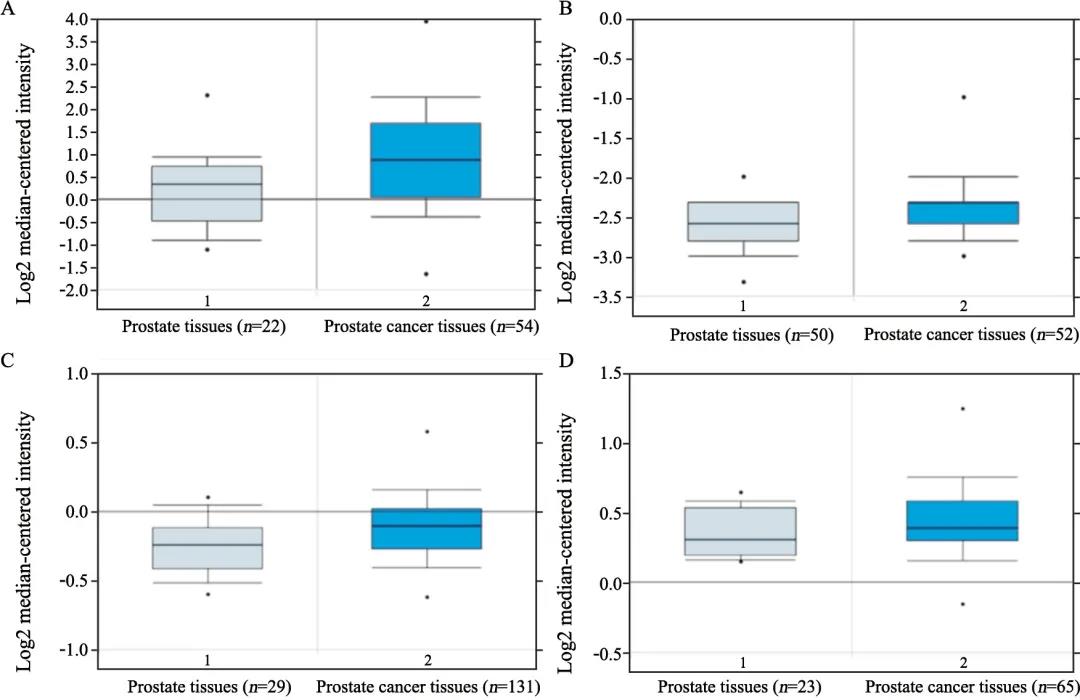

核受体肝细胞核因子4α(hepatocyte nuclear factor4α,HNF4α)作为重要的转录因子,其在前列腺癌中的作用及调控机制尚不清楚。探讨HNF...